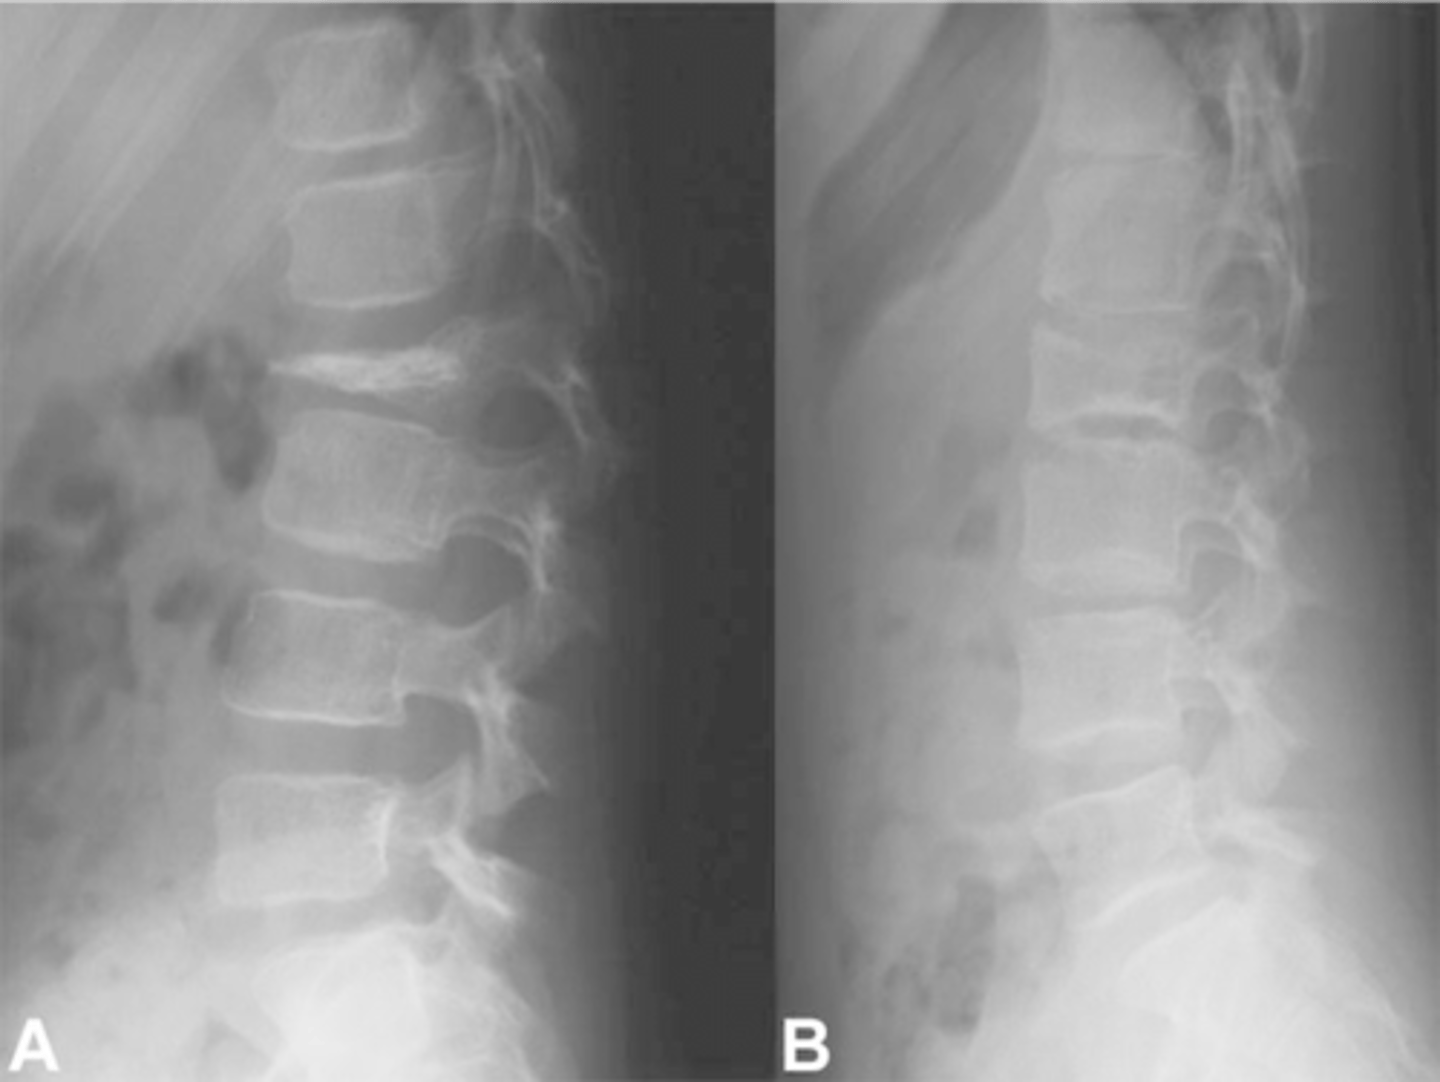

- Left: Paget Disease

- Middle: Vertebral hemangioma

- Right: Osteoporosis

Complete the DDx for vertebral hemangioma

<p>Complete the DDx for vertebral hemangioma</p>

- Vertical striations (corduroy cloth)

- Expansion (rare) may result in neurologic findings

- Skull ("sand dollar")

- Paravertebral swelling

State the radiographic features of vertebral hemangioma

<p>State the radiographic features of vertebral hemangioma</p>